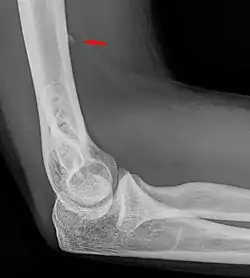

Larger supracondylar process seen on a lateral radiograph of the elbow

The supracondylar process of the humerus (also known as an avian spur) is a variant bony projection on the anteromedial aspect of the upper arm bone (humerus), about 5–6 cm above the medial epicondyle.[1] It is directed downward, forward and medially pointing to the medial epicondyle. A fibrous band, Struthers ligament, may connect this process to the medial epicondyle.[2] This variation has a prevalence of 0.68% and is significantly more common in women than in men.[3]